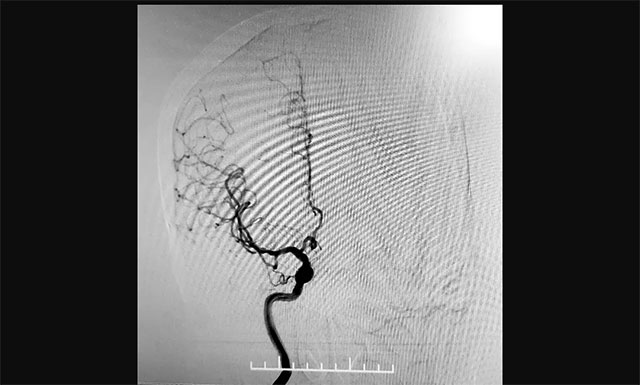

張琪博士在進(jìn)行DSA手術(shù)

▲ 張琪博士在進(jìn)行DSA手術(shù)